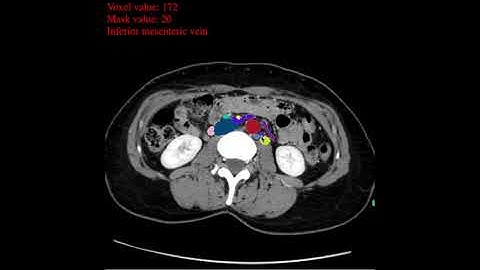

Tutorial video (CT): "Fat segmentation"